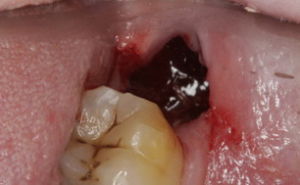

符合乾槽症臨床表現,拔牙窩內為腐敗變性的血凝塊,腐臭味強烈。非腐敗型

符合乾槽症臨床表現,拔牙窩內空虛,沒有明顯腐敗物存在。發病原因

主要症狀為拔牙2-3天后有劇烈疼痛,並可向耳顳部、下頜區、頭頂部放散,一般鎮痛藥物不能止痛;拔牙窩內可空虛,或有腐敗變性的血凝塊,有強烈腐臭味。疾病危害

主要依靠臨床表現進行診斷,疼痛發生的時間、誘因、程度,拔牙窩是否有空虛或腐敗壞死物,結合好發人群、口腔衛生情況、拔牙術後護理情況,進行診斷。疾病鑑別